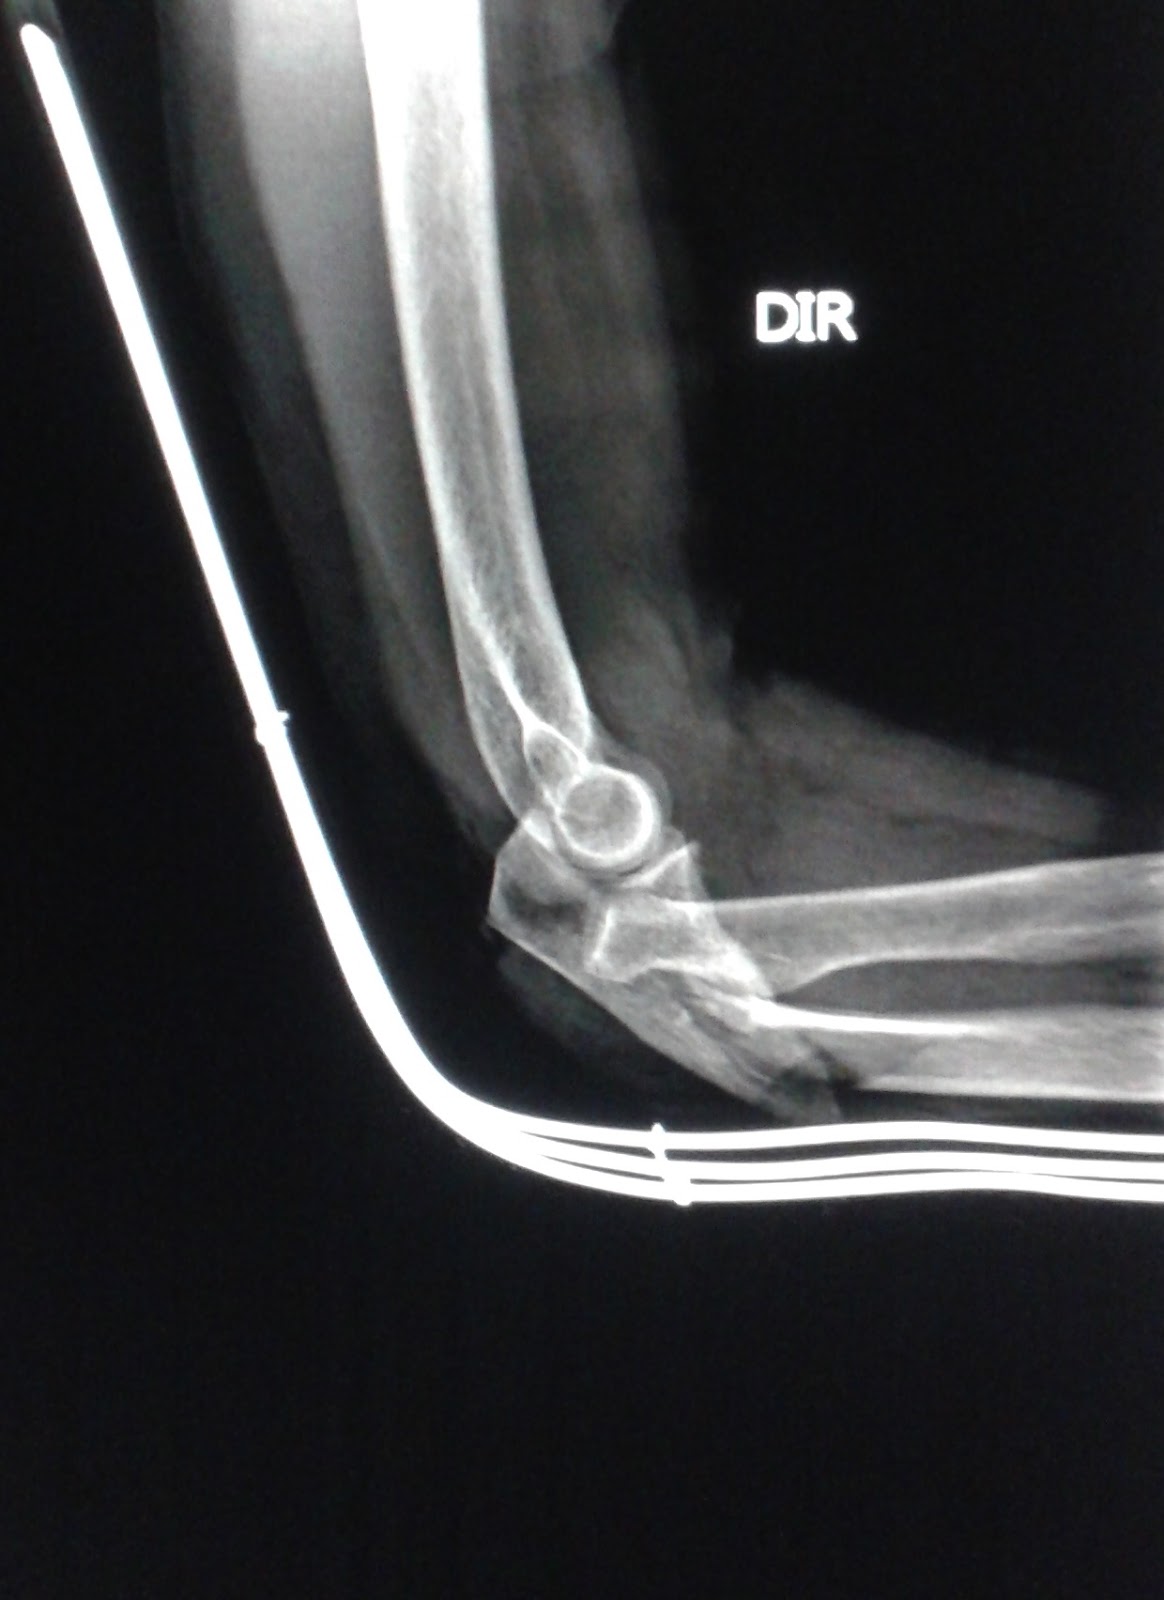

DICAS DE RADIOLOGIA Tudo Sobre Radiologia IMAGENS RADIOLÓGICAS FRATURA ULNA COTOVELO